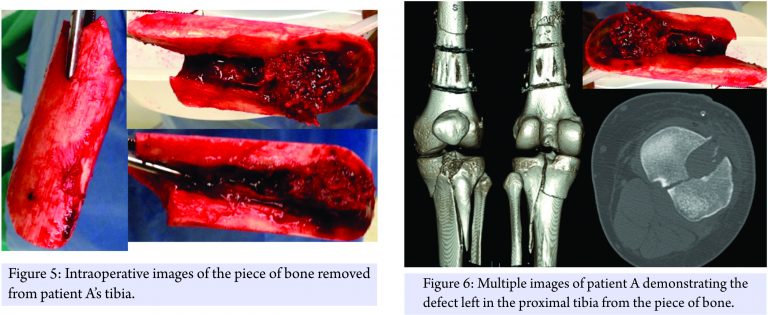

The decision was made to treat both patients operatively. First, patient A was taken to the operating room for an exploration and debridement of the left knee with there moval of the cortical piece of bone, followed by a retrograde intramedullary femoral nail. A spanning knee external fixator was placed to stabilize his tibial plateau fracture. The removed cortical fragment was identified as the missing piece of bone from the other patient’s femur (Fig. 5 and 6).

Patient B was then taken to the operating room for an irrigation and debridement of his left thigh and retrograde intramedullay nailing of his femur. The patella and femoral condyle fractures did not meet operative criteria. A long discussion was had with the patient and his family about how to best treat the bone loss from the femur. Due to the possibility of disease transmission, infection, and the fact that it was not involving the articular surface, the free piece of cortical bone was discarded. Since the patient was a young, healthy male with 50% apposition of intact femur, we decided to proceed with operative fixation of the femur without graft augmentation. A locked, retrograde femoral nail was used to stabilize the fracture (Fig. 7). Fig. 8 shows a side by side comparison of the extruded bone. He was made weight bearing as tolerated and was discharged home on post-operative day number 3.